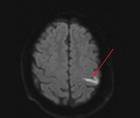

Stroke Snapshot: Intracranial MRI Vessel-Wall Imaging

Mitchell Barnes, DO; Parham Moftakhar, MDMitchell Barnes, DO; Parham Moftakhar, MD